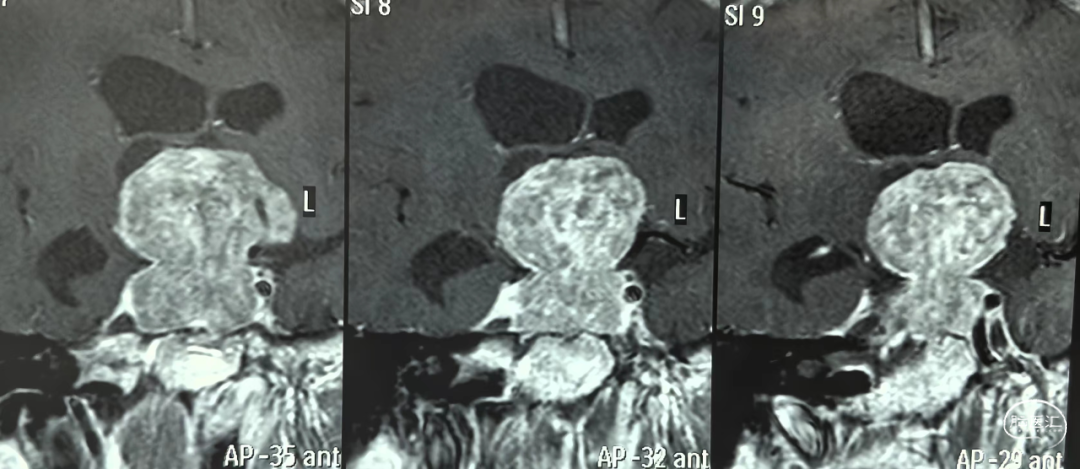

术前增强MRI